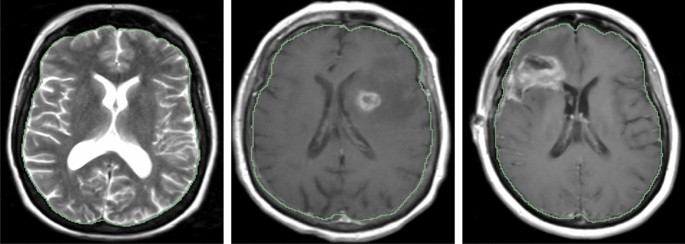

As discussed early, the proposed method works not only in healthy brain MRIs, but also in pre-/post- operative MRIs. To quantitatively evaluate the performance difference, we set up an experiment. The result is shown in Table 3. Interestingly, we noticed that the best results happened in pre-operative brain tumor MRIs, rather than in healthy brain MRIs. In addition, we also compute the t-test among different types of MRI, as shown in Table 3. The p-value of Healthy vs. Post-op, Healthy vs. Pre-op, and Pre-op vs. Post-op is 0.3869, 0.0204, and 0.2301, respectively. It indicates a significant performance difference between healthy and pre-operative MRIs, but no significant difference in rest cases. The reason may be that the training data is from the pre-operative mpMRIs with glioblastoma. Overall, the skull stripping performance is stable in all conditions, either the healthy brain MRIs, or brain tumor MRIs. There are 3 showcases shown in Fig. 3.